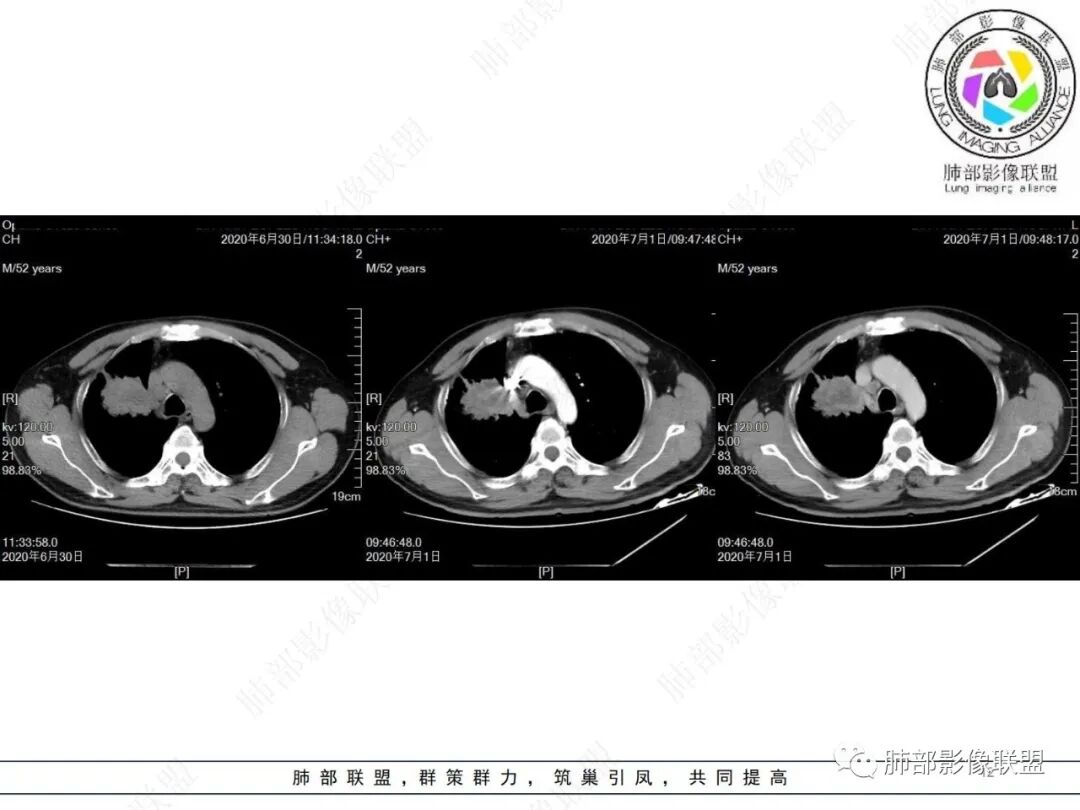

中年男性,有长期吸烟史,右肺上叶不规则肿块,边缘膨隆有分叶,支气管截断,不均匀强化,内有多灶性坏死,癌胚抗原升高,考虑肺癌可能性大,鳞癌可能。鉴别腺癌。

中年男性,吸烟病史,右肺前叶块状占位性病变伴前段支气管截断,病变周围可见结节及斑片状影,增强肿块不均匀性强化,纵隔淋巴结肿大,结合实验室检查,首先考虑肺小细癌,鉴别鳞癌、大细胞。

右肺上叶不规则形软组织密度肿块影,边缘见分叶,毛刺,病灶呈宽基底与胸膜相连,病灶内见坏死,增强扫描呈不均匀性强化,右肺上叶支气管截断,纵隔内见肿大淋巴结,肿瘤标志物增高,考虑鳞癌可能,鉴别小细胞癌,腺癌。

老年人,右肺上叶肺不张伴阻塞性炎症,右肺上叶支气管闭塞,增强病灶强化不均匀,可见边缘不清晰的坏死,纵膈淋巴结增大,考虑中央型肺癌,鳞癌可能性大。

右肺上叶不规则肿块,分叶、毛刺,上叶支气管截断,断端圆钝,不均匀强化,其内空泡及坏死,坏死边界不清,考虑腺癌或腺鳞癌,鉴别鳞癌

右肺上叶团块影,边缘膨隆,支气管近端截断,肿块内密度不均匀,见片状坏死,边界不清,纵隔肿大淋巴结,CEA明显增高,考虑恶性,鳞癌?腺鳞癌?

中年男性,长期吸烟,CT示右肺上叶肿块影,有分叶,毛刺,胸膜牵拉,支气管截断,边缘斑片影,病变内有坏死,强化,淋巴结肿大,首先考虑鳞癌可能性大,鉴别腺鳞癌

右肺上叶占位,支气管阻塞截断,病变周围可见结节及斑片状影,密度不均,坏死边缘不清,纵隔淋巴结肿大,中年男子,吸烟史,考虑鳞癌、腺鳞癌,鉴别结核

沼泽样坏死,支气管截断,周围阻塞性炎症,并淋巴道水肿,考虑腺鳞癌,鳞癌

右上叶支气管截断呈斜坡状,不均匀强化,低密度区实质区边界不清,老年男性,长期吸烟史,考虑恶性,鳞癌首选

长期抽烟的老头,右肺上叶不规则肿块,边缘膨隆有分叶,支气管截断,不均匀强化,内有片状坏死,考虑肺癌,常规思路鳞癌可能。鉴别腺癌。

中年男性,长期吸烟,右肺上叶不规则肿块,边缘膨隆有分叶,支气管截断,不均匀强化,内有多灶性坏死,癌胚抗原升高,考虑肺癌